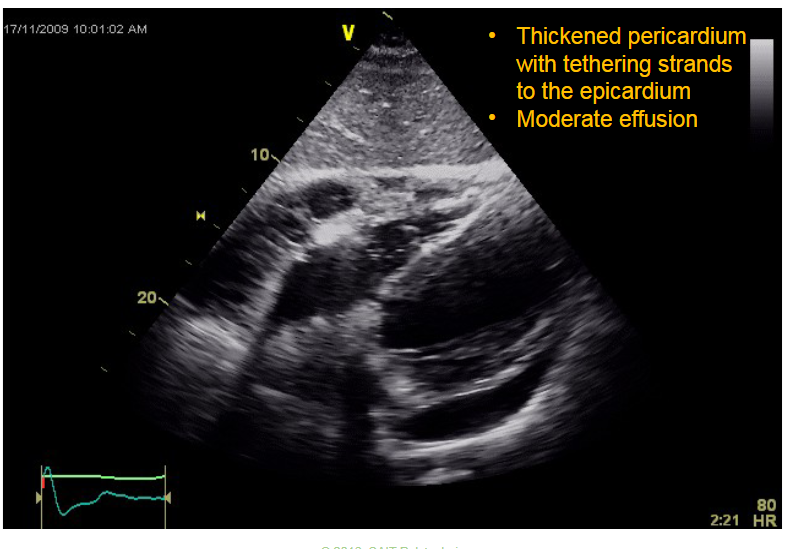

Q

What does this image represent?

A

Pericarditis with constriction